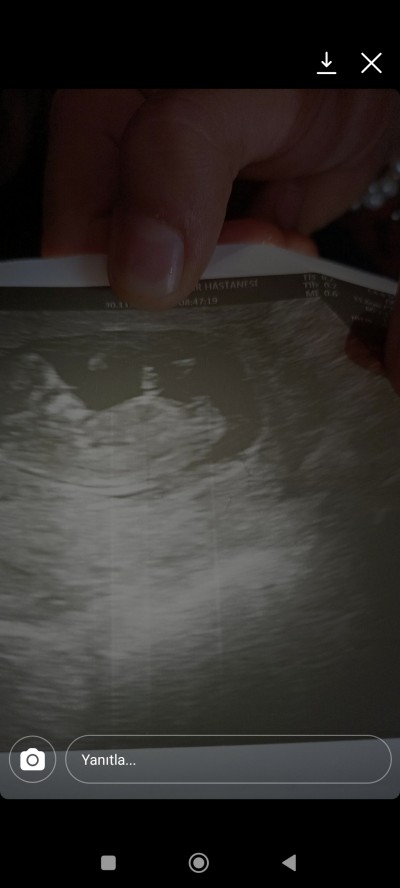

doktor kız dedi ama pek emin değilim dedi bacağın arasındaki cikintiyi dikkatli bakar msiniz

Kız bebek, sağlıkla alın kucağınıza. Nub çıkıntısından belli kız olduğu. :)